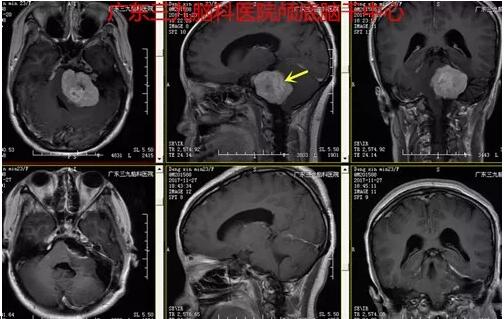

图4:术前术后MR对比